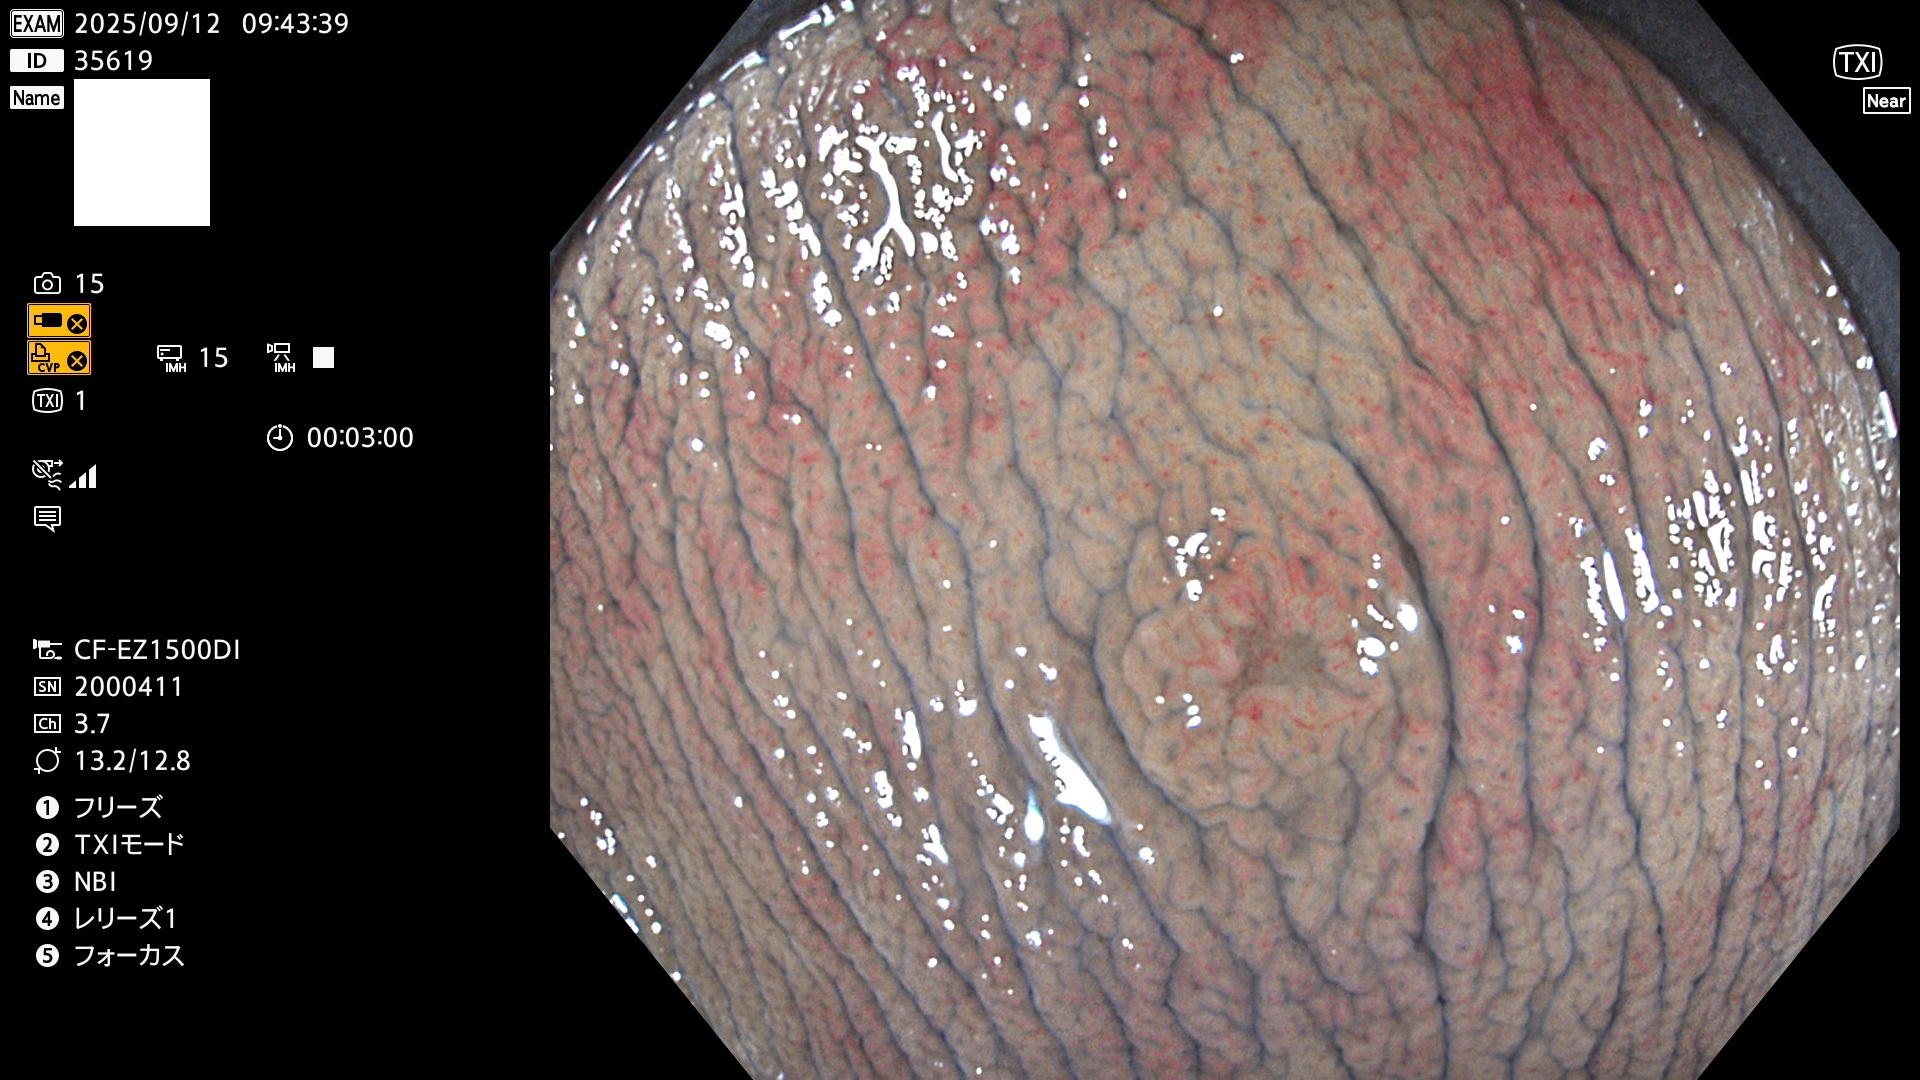

完全に平坦な物をUb、陥凹している物をUcと呼びます。Ubは認識が困難で、Ucはびらん(炎症)と紛らわしいために見落とされやすく、「内視鏡後・大腸癌」の原因になります。

専門的)Uc=De Novo癌? 内視鏡の解像度が低かった時代、このような説もありました。しかし今日の高精度内視鏡では良性の微小なUc型腺腫(APC遺伝子異常の腺腫)が日常的に見つかります。Ucこそが多段階発癌(Adenoma-Carcinoma Sequence)のMain Routeです。

専門的)細胞生物学的Ucの再定義UcをPitと形態学で定義するのは医学的には全く不毛です。Ucの本質はIntraTumor HeterogenityとTumor Dormancyが微小病変に見られる点です。これは早い腫瘍進化=ゲノム不安定性を意味します。そのような病変は隆起型でも形態によらずUcと定義すべきです。なぜなら1年後には陥凹し典型的Uc(最悪の場合NPG癌)になるからです。

2025年9月11日〜9月14日の4日間(40件)7個 (Uc_ADR=7個/40人=18%)